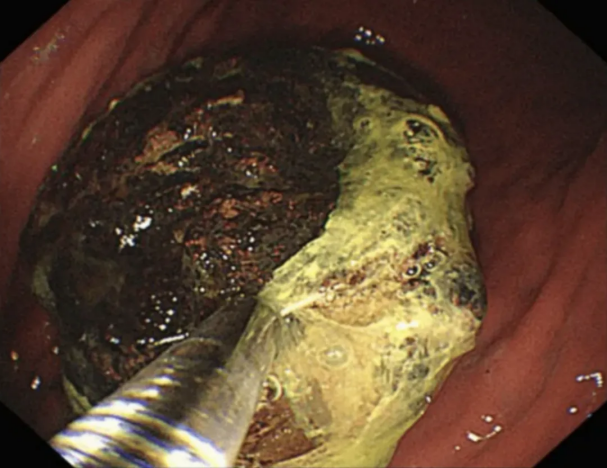

二、较大或顽固性胃石:内镜下碎石是首选

当胃石直径超过3~4厘米、药物无效或出现明显症状时,内镜治疗是主流微创方案 。

操作方式:通过胃镜送入活检钳、圈套器或激光设备,将胃石机械切割、捣碎成小块。

优势:创伤小、恢复快、可同时评估胃黏膜损伤情况(如溃疡、出血)。

后续处理:碎石后小块可自然排出,部分可通过网篮直接取出。特别提醒:毛发性胃石(如吞食毛发形成)必须完全取出,不能仅碎石排出。